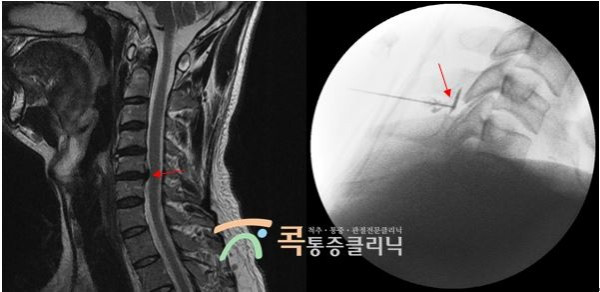

이번에는 움직이기 어려울 정도로 심한 목 통증으로 콕통증클리닉을 찾으셨던 환자분의 치료 사례를 알려드릴게요. 단지 심한 근육통일 것이라고 예상하신 환자분이셨는데요. MRI 검사 결과 급성 목디스크가 확인되었습니다. CI 시술을 진행하고 시술 후 상태가 매우 호전되셔서 현재는 통증이 거의 없는 상태이십니다. 재발 방지를 위해 도수치료와 물리치료를 시행하시며 경과를 관찰하고 있답니다.

CI시술이란 대학병원에서도 자주 사용되는 척추치료방법인데요. 특수 영상장치를 활용하여 경막 외 공간에 주사치료를 시행하는 시술이랍니다. 디스크 급성기의 방사통을 치료하는 데 통증 감소가 뛰어나며 수술적 치료에 비해서 상대적으로 간편하고 안전하다는 것이 큰 장점입니다. 또한 신경염증을 효과적으로 줄여 재발 방지를 할 수 있습니다. 일반적인 통증만 감소시키는 주사가 아니라 원인을 직접 치료하는 방법의 시술이죠.